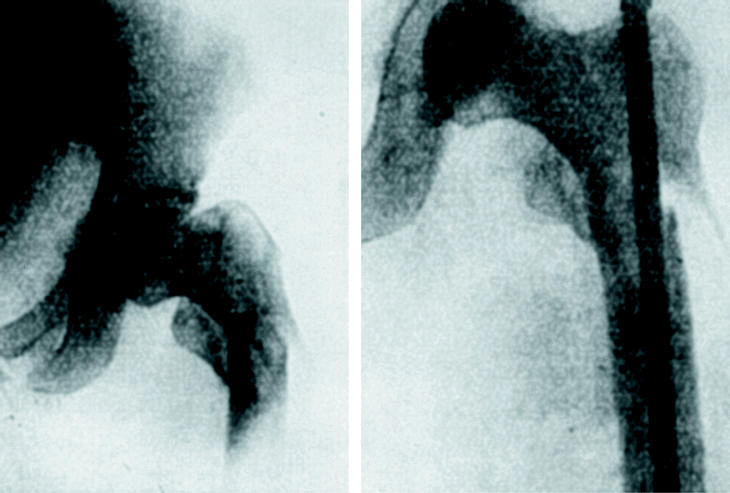

No tardó en percatarse de que el clavo era inestable en las fracturas proximales de fémur y en su afán de disponer un clavo adecuado para cada tipo de fractura, desarrolló un clavo cónico, para el tratamiento de fracturas pertrocantéreas y subtrocantéreas (Fig. 7) que, en 1940, cambió por un clavo bifurcado con una hendidura en la porción diafisaria que denominó en «Y» (Fig. 8), rudimento de lo que mucho más tarde sería el clavo gamma.

Figura 7. Radiografía de un clavo intramedular cónico.

Figura 8. Clavo intramedular en «Y».